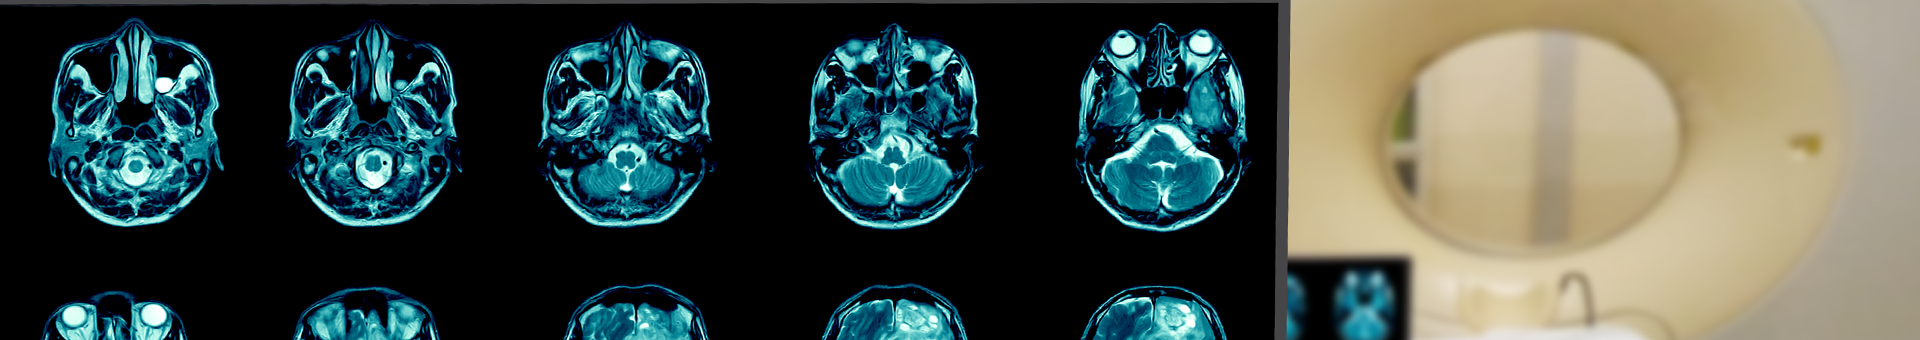

• CT Simulation procedure – palliative WBRT

VERT and ECLIPSE data set

• Open whole brain plan

• Create the plan and DVH